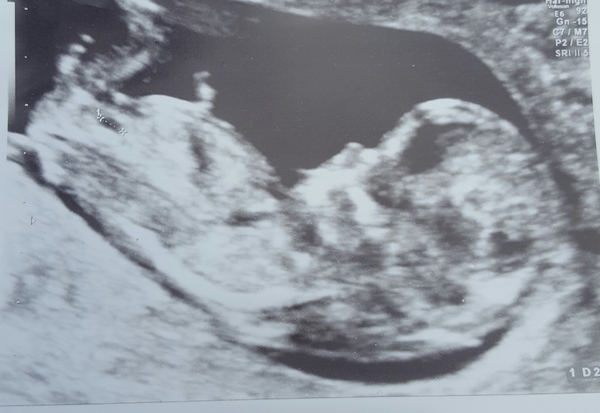

Mummyagainmaybe · 08/05/2017 22:00

First scan today. Appears healthy :)